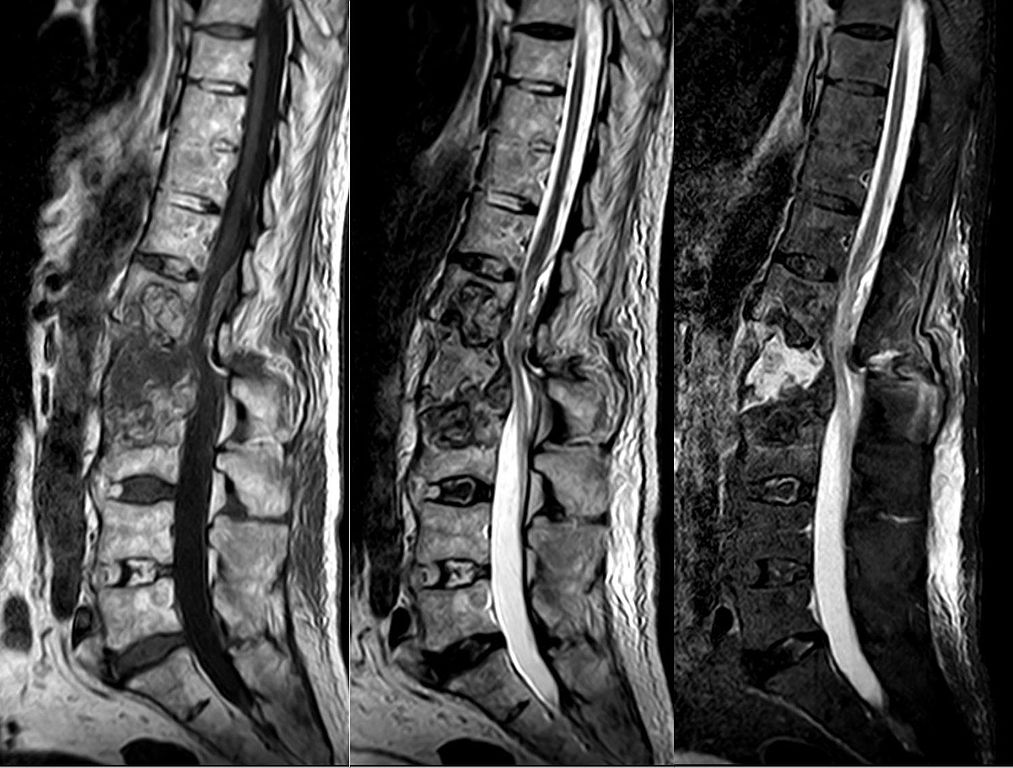

(PDF) Spondyloartritis en ankyloserende spondylitis (AS)...• ankyloserende spondylitis (de